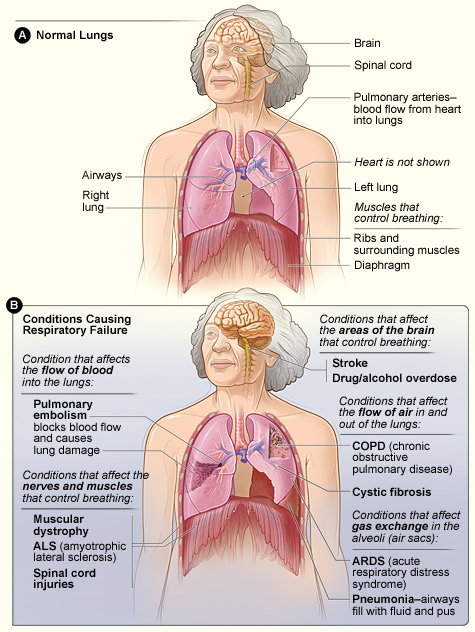

Causes of Respiratory Failure: can occur due to issues in any pathological or anatomical parts of the respiratory system.

- Central Nervous System – any condition that affects or lowers the conscious level.

- Peripheral Nervous System – any condition that affects the peripheral neural system (e.g. Guillain-Barré syndrome (GBS), nerve or spinal injury)

- Musculoskeletal System – any condition that affects the musculoskeletal part of the body (e.g. rib fractures, neuromuscular blockade)

- Airway Pathology – any condition that affects the airways (e.g. tumor, foreign body or laryngospasm)

- Pleural Pathology – any condition that affects the pleural parts of the lungs (e.g. haemothorax, pneumothorax or effusions)

- Pulmonary Pathology – any condition that affects the lungs (e.g. pulmonary fibrosis, pulmonary oedema, ARDS)

- Vasculature – any condition that affects vascular parts of the lungs (e.g. pulmonary embolism)

B – shows the major conditions that cause respiratory failure.